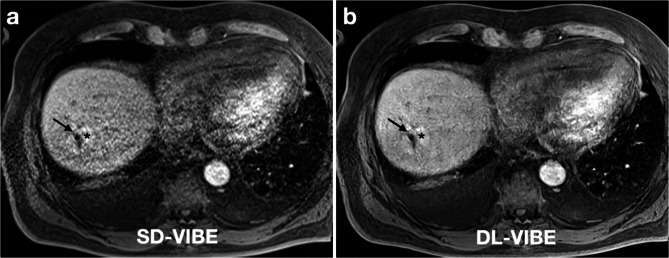

Objective: This study evaluates the impact of deep learning-enhanced T1-weighted VIBE sequences (DL-VIBE) on image quality and procedural parameters during MR-guided thermoablation of liver malignancies, compared to standard VIBE (SD-VIBE).

Methods: Between September 2021 and February 2023, 34 patients (mean age: 65.4 years; 13 women) underwent MR-guided microwave ablation on a 1.5 T scanner. Intraprocedural SD-VIBE sequences were retrospectively processed with a deep learning algorithm (DL-VIBE) to reduce noise and enhance sharpness. Two interventional radiologists independently assessed image quality, noise, artifacts, sharpness, diagnostic confidence, and procedural parameters using a 5-point Likert scale. Interrater agreement was analyzed, and noise maps were created to assess signal-to-noise ratio improvements.

Results: DL-VIBE significantly improved image quality, reduced artifacts and noise, and enhanced sharpness of liver contours and portal vein branches compared to SD-VIBE (p < 0.01). Procedural metrics, including needle tip detectability, confidence in needle positioning, and ablation zone assessment, were significantly better with DL-VIBE (p < 0.01). Interrater agreement was high (Cohen κ = 0.86). Reconstruction times for DL-VIBE were 3 s for k-space reconstruction and 1 s for superresolution processing. Simulated acquisition modifications reduced breath-hold duration by approximately 2 s.

Conclusion: DL-VIBE enhances image quality during MR-guided thermal ablation while improving efficiency through reduced processing and acquisition times.